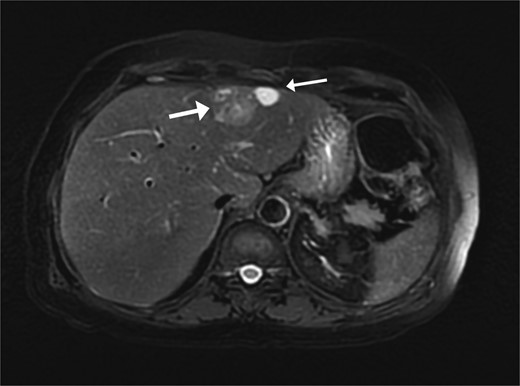

A 74-year-old man with right-handed colon cancer presented at the Emergency Department with a symptomatic anemia following chemotherapy and surgical intervention one year prior to the hepatocellular carcinoma resection. He reported 1-month history of paleness, dizziness, and exertional dyspnea, and fatiguability. Physical examination results were unremarkable. A chest CT angiography did not reveal a pulmonary embolism; however, two hepatic lesions, measuring 3.5 cm and 1.5 cm, in segment II were noted incidentally. Therefore, further laboratory tests were performed; hepatitis C virus was detected with a liver cirrhosis Child-Pugh score indicating class A disease; however, no tumor markers were detected. An abdominal CT revealed the two hepatic lesions in segment II, the larger lesion (3.8 cm × 3.4 cm) demonstrated arterial enhancement and faint washout in the delayed phase (Fig. 1). The smaller lesion measured 1.2 cm × 1.1 cm (Fig. 1). An abdominal MRI was performed to characterize the hepatic lesions: one lesion was consistent with HCC and the second was metastatic from mucinous which was visible previously on imaging at the time of diagnosis of colon cancer (Fig. 2). Furthermore, the biopsy of the two liver lesions confirmed the diagnoses of HCC and metastatic colon cancer. Subsequently, the case was discussed within a multidisciplinary tumor board (MDTB), where the decision was made to perform chemotherapy and trans arterial chemoembolization for the HCC lesion. Upon follow-up evaluation, segment II hepatic lesion size had decreased to 1.6 × 2.4 cm (previously was 3.8 × 3.4 cm) and 1.5 × 1.3 cm (previously 1.2 × 1.1 cm). Consequently, the case was rediscussed in MDTB, and it was decided to proceed with liver resection of the two lesions. Following this, the patient underwent left lateral lobectomy, common hepatic artery dissection, porta hepatis lymph node dissection, and cholecystectomy. Postoperative pathology showed a residual 2.3-cm-sized differentiated HCC and a metastatic colonic-type adenocarcinoma with a mucinous differentiation which was 1.2 cm in size. The two lesions measured 0.7 cm apart (Fig. 3). All lymph nodes dissected from the porta hepatis, and the common hepatic artery were positive for metastatic colonic type adenocarcinoma. The patient’s postoperative course was unremarkable, and he was discharged 12 days later. Following a discussion within the MDTB, it was decided to continue adjuvant chemotherapy.

Two segment II hepatic lesions: the larger lesion is consistent with clear cell variant hepatocellular carcinoma and the second, more cranial lesion, is likely metastasis from a mucinous adenocarcinoma.